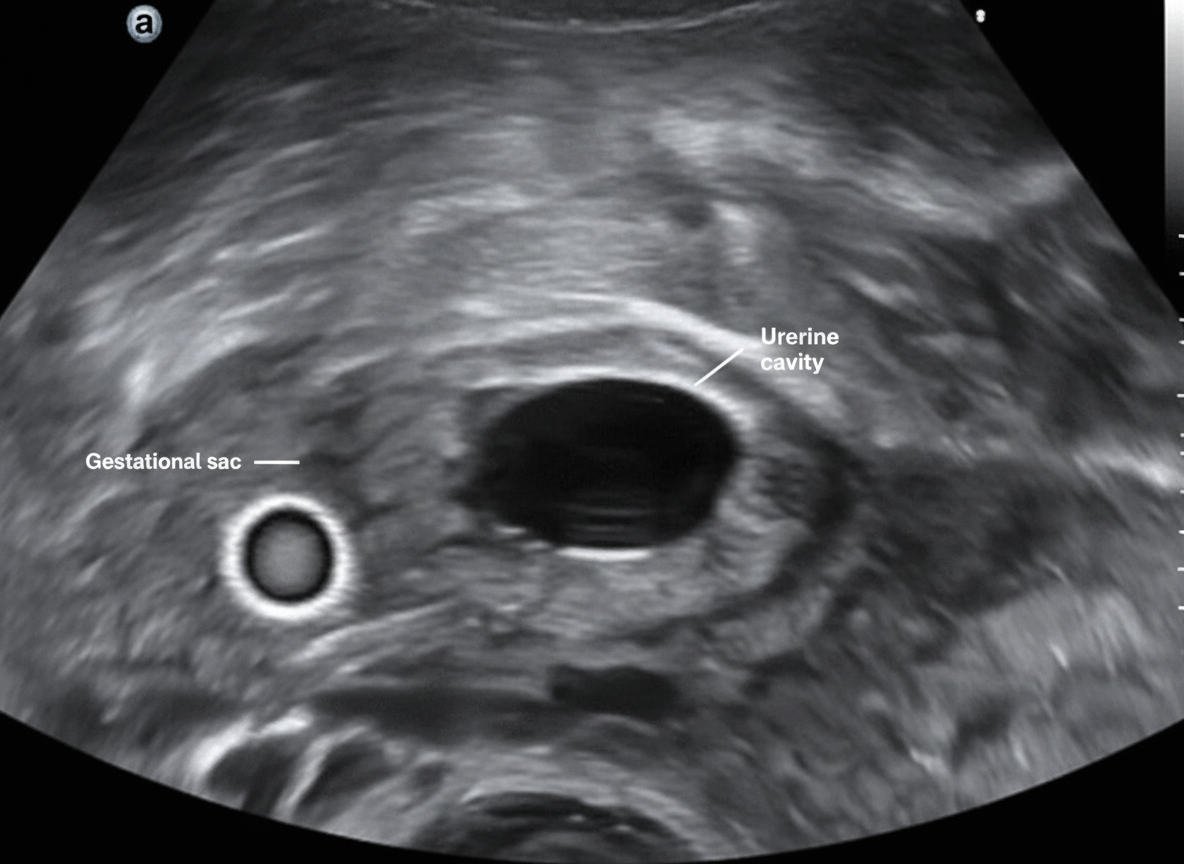

Which of the following conditions is NOT associated with the pathology shown in the ultrasound image?

Explanation: ***Clomiphene citrate therapy*** - **Clomiphene citrate** is a selective estrogen receptor modulator that induces ovulation by blocking estrogen receptors at the hypothalamic level, but it does **NOT increase the risk of ectopic pregnancy**. - Unlike **gonadotropin therapy** (which does increase ectopic pregnancy risk), clomiphene has a **normal rate of tubal implantation** and does not affect fallopian tube function or motility. *Salpingitis* - **Pelvic inflammatory disease (PID)** and salpingitis cause **tubal scarring** and **adhesions**, leading to impaired tubal motility and increased risk of ectopic pregnancy. - **Chlamydia** and **gonorrhea** infections are major causes, resulting in **tubal damage** that prevents normal embryo transport to the uterus. *Intrauterine contraceptive device (IUCD)* - **IUCD use** increases the risk of ectopic pregnancy by causing **local inflammatory changes** in the endometrium and fallopian tubes. - While IUCDs prevent intrauterine pregnancy more effectively than tubal pregnancy, the **relative risk of ectopic pregnancy** is increased in IUCD users who do conceive. *Plastic procedure on the fallopian tube* - **Tubal reconstructive surgery** (salpingoplasty, salpingostomy) can cause **tubal scarring** and **adhesion formation**, impairing normal tubal function. - **Previous tubal surgery** disrupts the normal **ciliary action** and **muscular contractions** of the fallopian tube, increasing ectopic pregnancy risk.